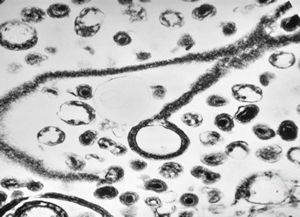

M,3m. | Pneumocystis carinii